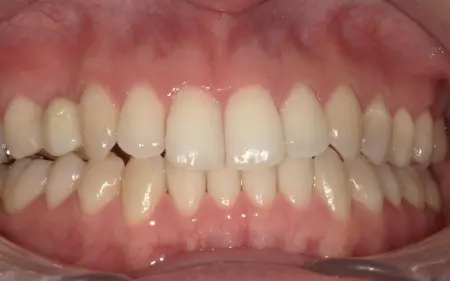

2025.11.0920代女性 マルチブラケット装置やヘッドギアを併用した矯正治療で出っ歯を改善した症例